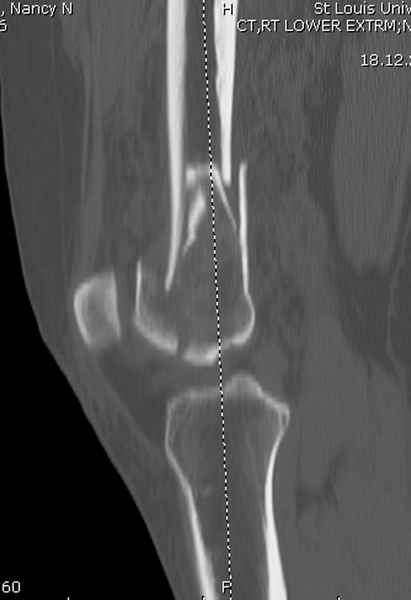

Приветствую всех коллег!!Во первых слева хотелось бы видеть четкую боковую проекцию а лучше КТ. По р-мам есть сомнения насчет повреждения суставной поверхности. При подобных переломах даже внутрисуставных без смещения хорошие результаты показал закрытый ретроградный остеосинтез универсальным бедренным стержнем Деост.Кстати при внутрисуставном переломе возможно применение вместо винтов стягивающих болтов!!(См. метод.Деост).При переломе справа также стержень Деост. Однако без открытия Вам не удастся устранить интерпозицию, только промучаетесь!Из минимального разреза удалите интерпозициб и фиксируйте стержнем. Причем универсальный стежень Деост позволяет фиксировать дистально минимум на трех уровнях!

Мы бы не стали открывать, такие переломы срастаются, хотя бы и с краевым дефектом. То есть если удалять стержень потом, то сильно попозже обычного. В приложении пример. Сразу после операции и через 11 мес. Понятное дело, пациент к тому времени давно и не хромал, и функция колена была полная.